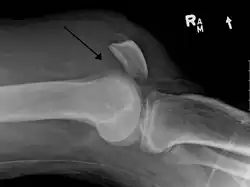

| An x-ray demonstrating quadriceps tendon rupture. Note the abnormal angle of the patella and soft-tissue swelling marked by the arrow. | |

A quadriceps tendon rupture is a tear of the tendon that runs from the quadriceps muscle to the top of the knee cap.[1]